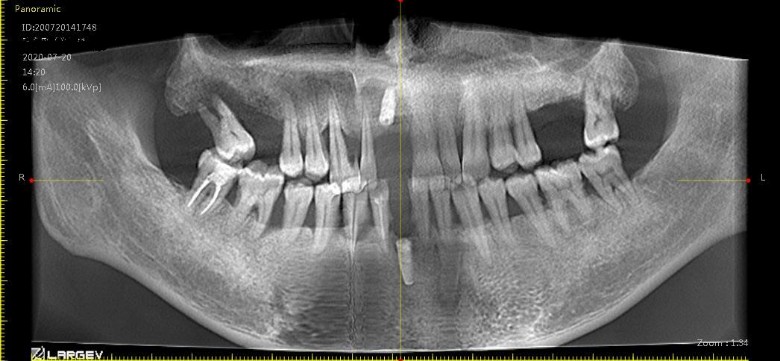

LZ在三院周主任那种的吗,她的号好难挂,我有颗牙齿掉了一半,估计也只能拔掉种植了